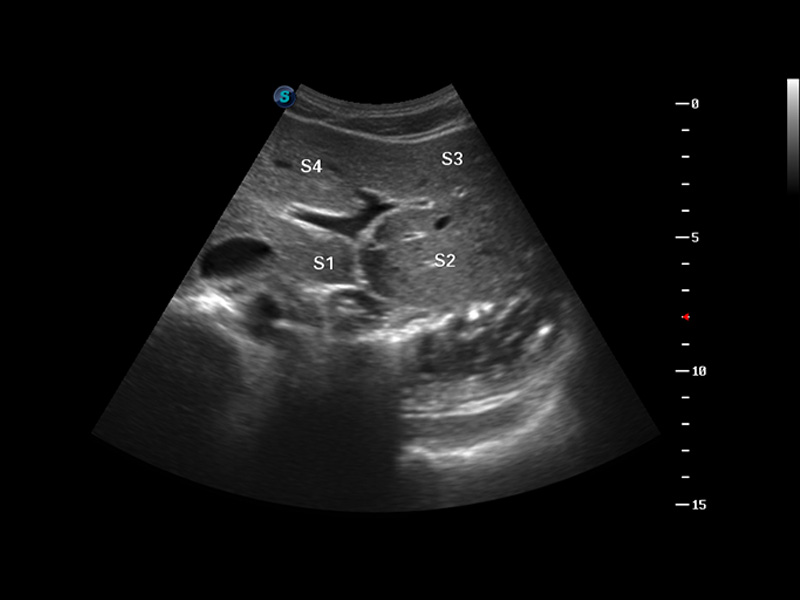

S8 EXP便攜式彩色多普勒超聲診斷儀是開立醫(yī)療研發(fā)的高端全身應(yīng)用型便攜彩超。高通道的VIS平臺融合可視化(Visual)、智能化(Intelligent)和人性化(Smart)的特點,配以開立醫(yī)療自主研發(fā)生產(chǎn)的探頭大家族,使您能夠快速、準確的獲得病人信息,提高工作效率的同時減輕疲勞。

成像技術(shù)

多波束形成器

諧波成像

空間復(fù)合成像

3D/4D成像